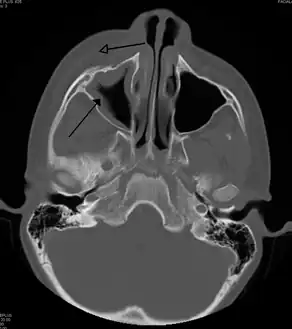

![]() | |

| A CT scan showing sinusitis of the ethmoid sinus | |